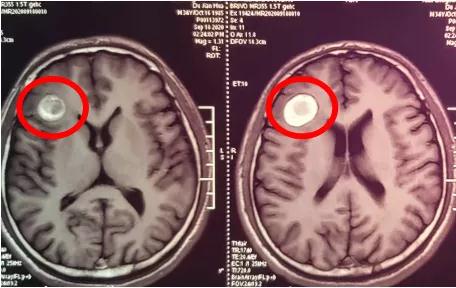

患者住院后,外科张强主任组织神经外科小组,ICU、麻醉科及精神科相关医务人员进行讨论,制定合理可行的手术方案。开颅术前先行脑血管造影排除脑动静脉畸形,进一步确诊为海绵状血管瘤,故首选开颅手术。

1月27日,在我院层流手术室,由王宏主任医师主刀,贾杉、张海鹏主治医师协助。手术通过术前的精确定位,选择右侧额颞部手术切口,在内镜辅助下,经右侧额下回前部脑沟小皮质窗,完整全切肿瘤。